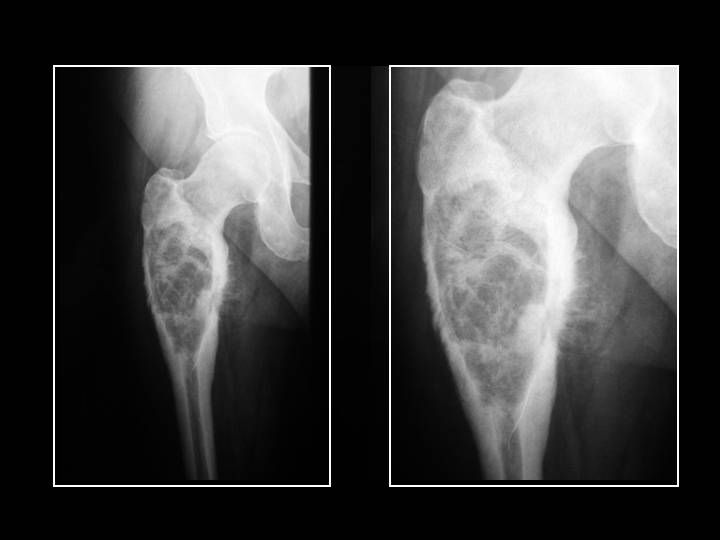

- Osteosarcoma: Osteosarcoma (sarcoma osteogenetico) è il secondo più comune tumore maligno dell'osso. È più comune tra individui che vanno dai 10 ai 25 anni di età, sebbene che possa capitare a tutte le età. L'Osteosarcoma produce osteoidi maligni (osso immaturo). Solitamente si sviluppa intorno al ginocchio (femore distale più frequente di quello prossimale di tibia) o in altre ossa lunghe, specialmente in regione metafiso-diafisaria e può metastatizzare, solitamente al polmone o ad altre ossa [4]. Il dolore e il gonfiore locale sono i sintomi usuali.

- Aspetto litico, distruttivo

- Bordi irregolari del tumore

- Aree di distruzione ossea

- Distruzione delle corticali

- Invasione dei tessuti soffici circostanti

- Fratture patologiche